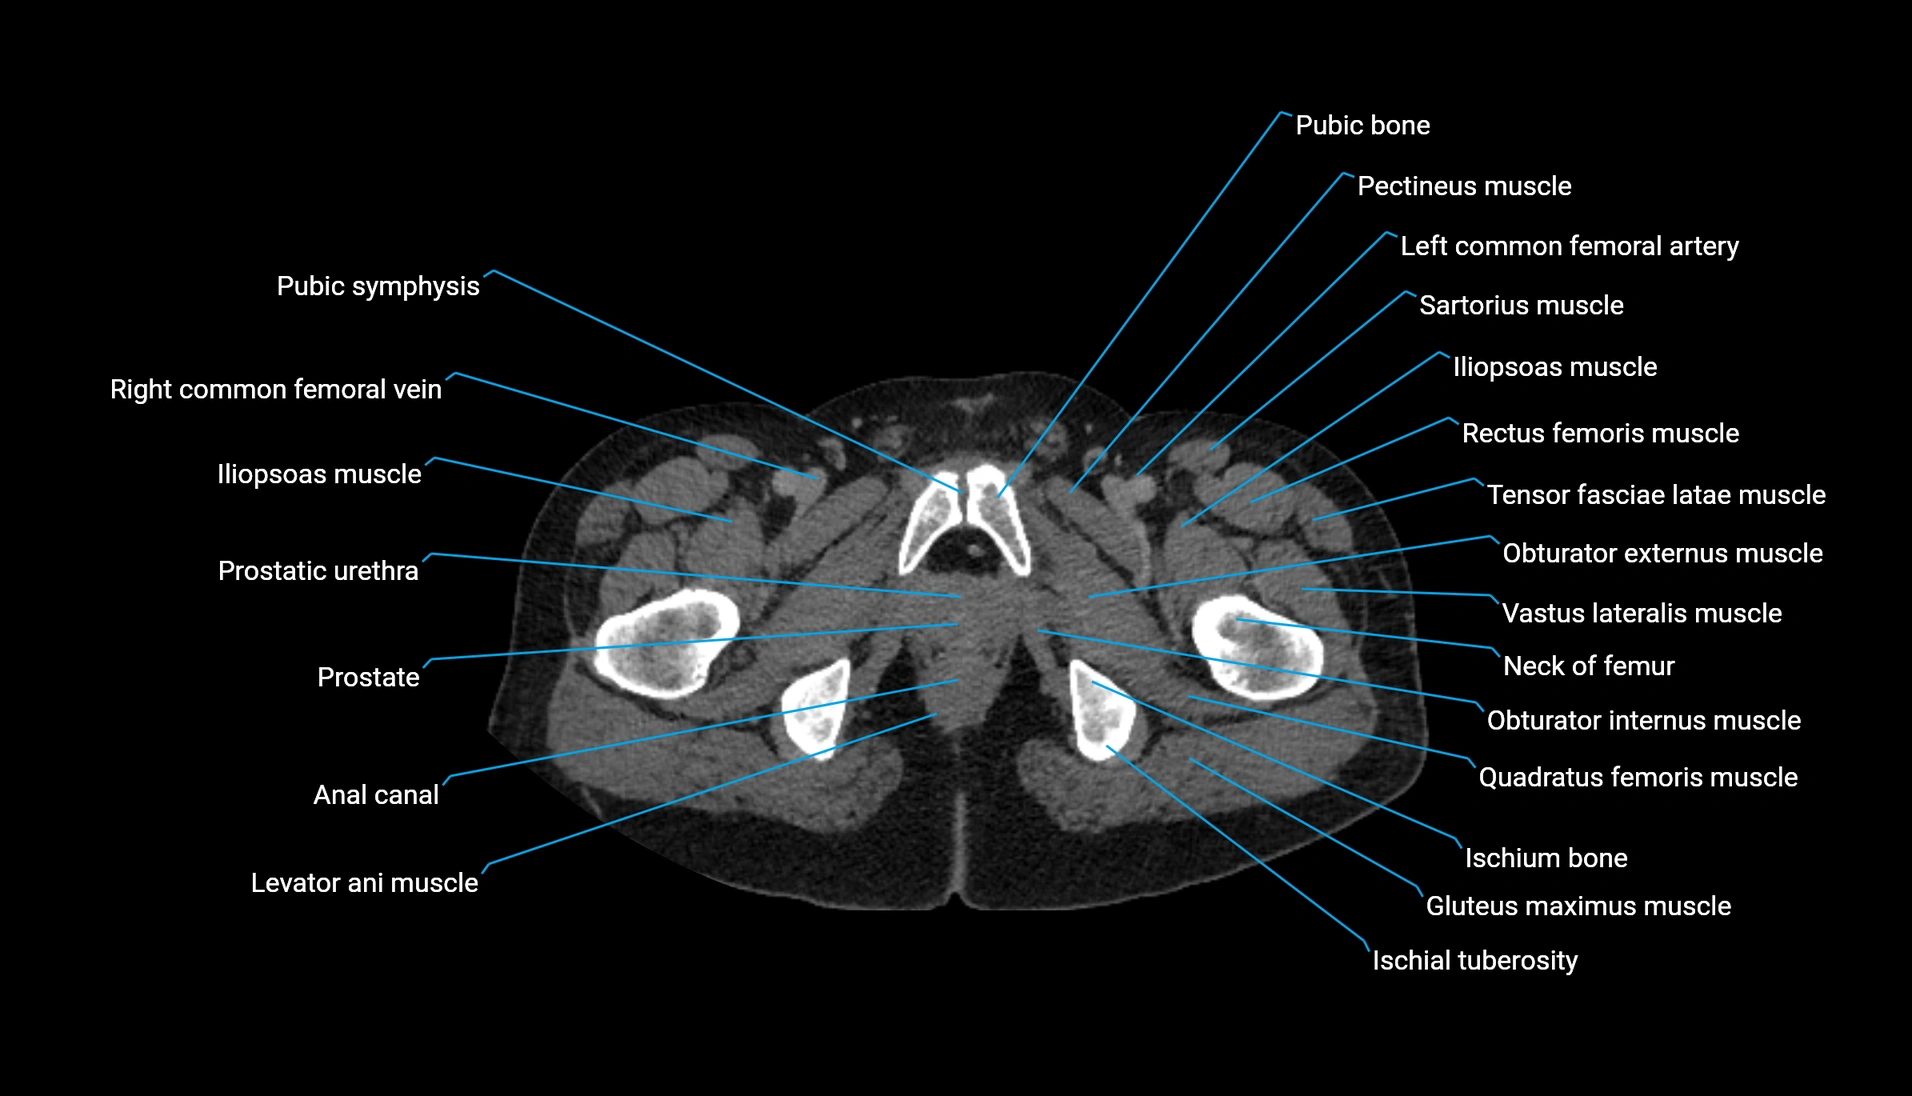

CT Appearance

Non-contrast CT:

-

Demonstrates cortical bone of acetabular rim in excellent detail

Detects fractures, dysplasia, retroversion, or bony overcoverage (pincer impingement)

3D reconstructions used in preoperative hip surgery planning

CT VRT 3D image

CT image